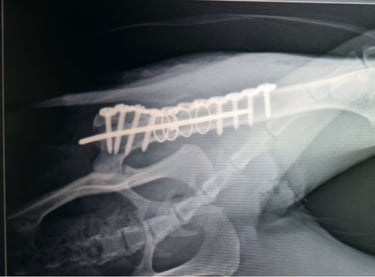

Meet Moeinza, a 4-year-old cat who survived a fall from the fourth floor. The accident left her with a severe upper femur fracture, broken into three complex pieces.

A 3D CT scan showed the extent of the damage, but her recovery was never in doubt. Under the care of Dr. Anil and Dr. Avinash, Moeinza underwent an intricate orthopedic surgery where her femur was reconstructed using a plate, screws, K-wire, and an intramedullary nail.

Her X-rays, from the initial fracture to the post-surgery results, reflect precision, teamwork, and commitment to animal care.